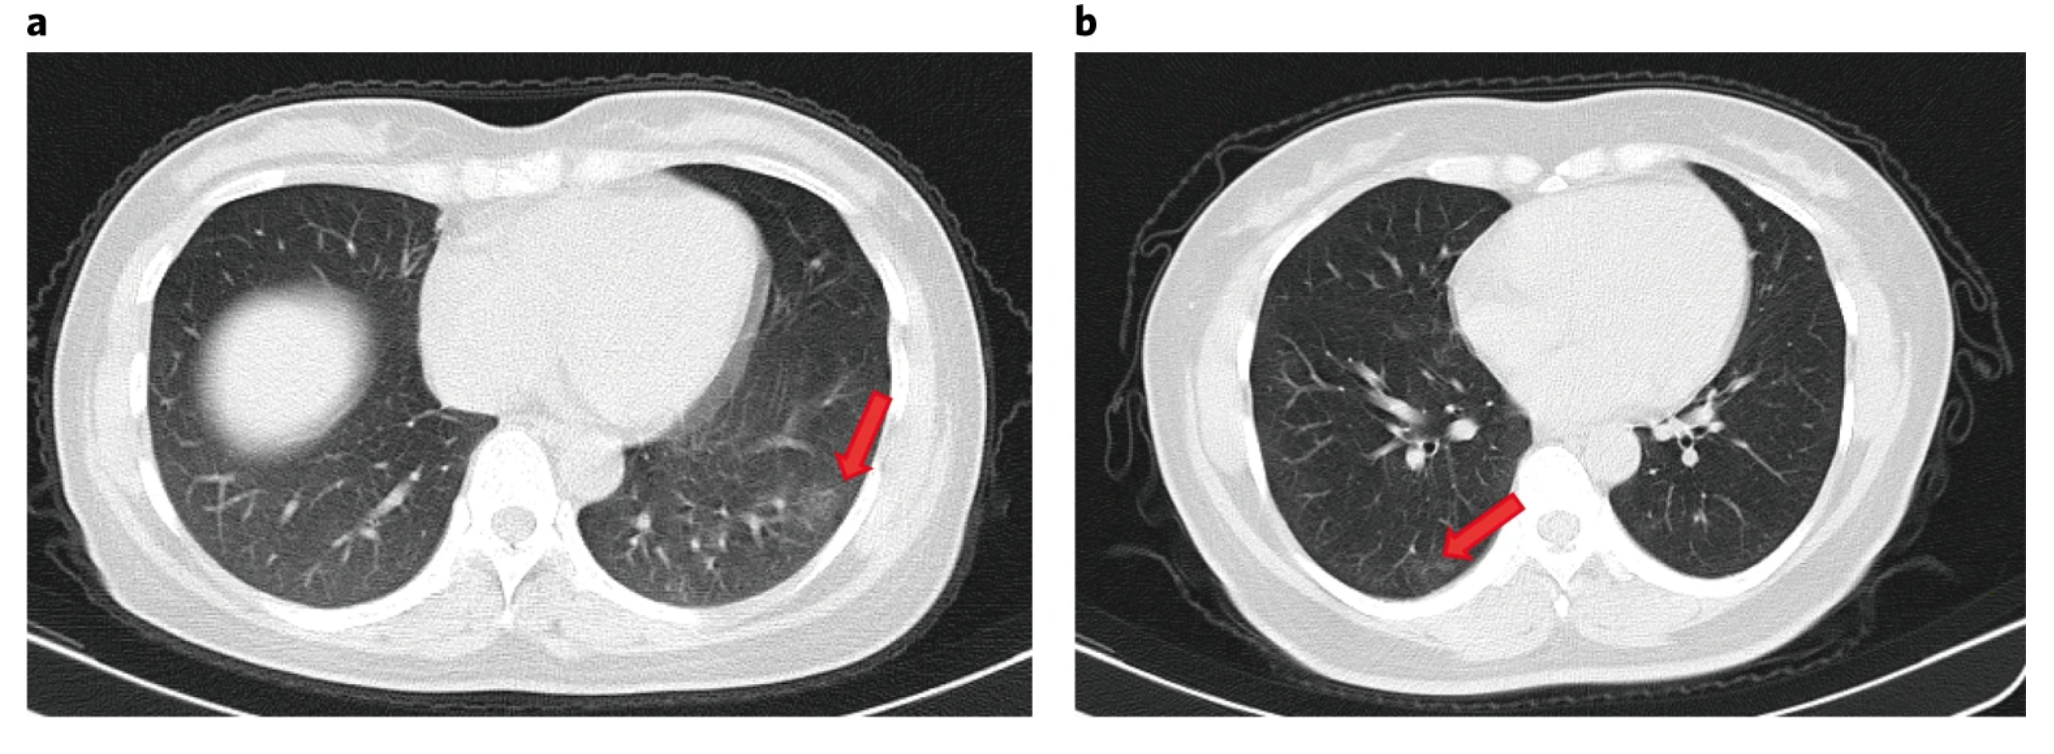

Las personas asintomáticas parecen representar aproximadamente del 40% al 45% de las infecciones por SARS-CoV-2, y pueden transmitir el virus a otras personas durante un período prolongado, quizás más de 14 días. La infección asintomática puede estar asociada con anomalías pulmonares subclínicas, como se detecta mediante tomografía computarizada. Debido al alto riesgo de propagación silenciosa por personas asintomáticas, es imperativo que los programas de prueba incluyan a aquellos sin síntomasAnnals of Internal Medicine  3 de junio de 2020